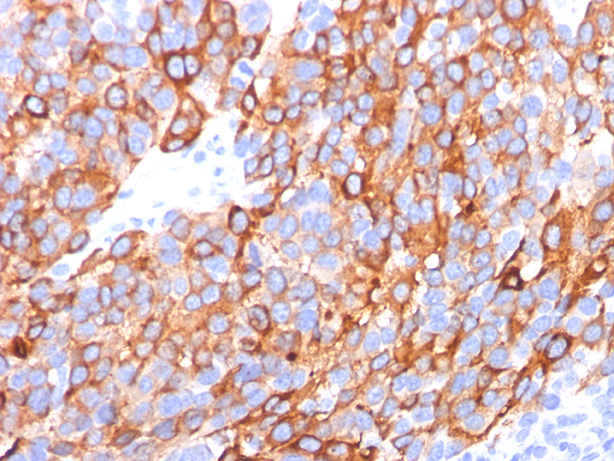

Formalin-fixed, paraffin-embedded human melanoma stained withMelan-A MAb (A103+M2-7C10+M2-9E3). Note cytoplasmic staining of cells. |